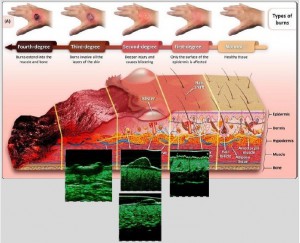

-Κύριες παθολογικές διεργασίες

-Μέθοδοι θεραπείας υψηλής ενέργειας

(λέιζερ, RF-Ραδιοσυχνότητα, HIFU-Υψηλής Έντασης Εστιασμένος Υπέρηχος, κ.λπ.)